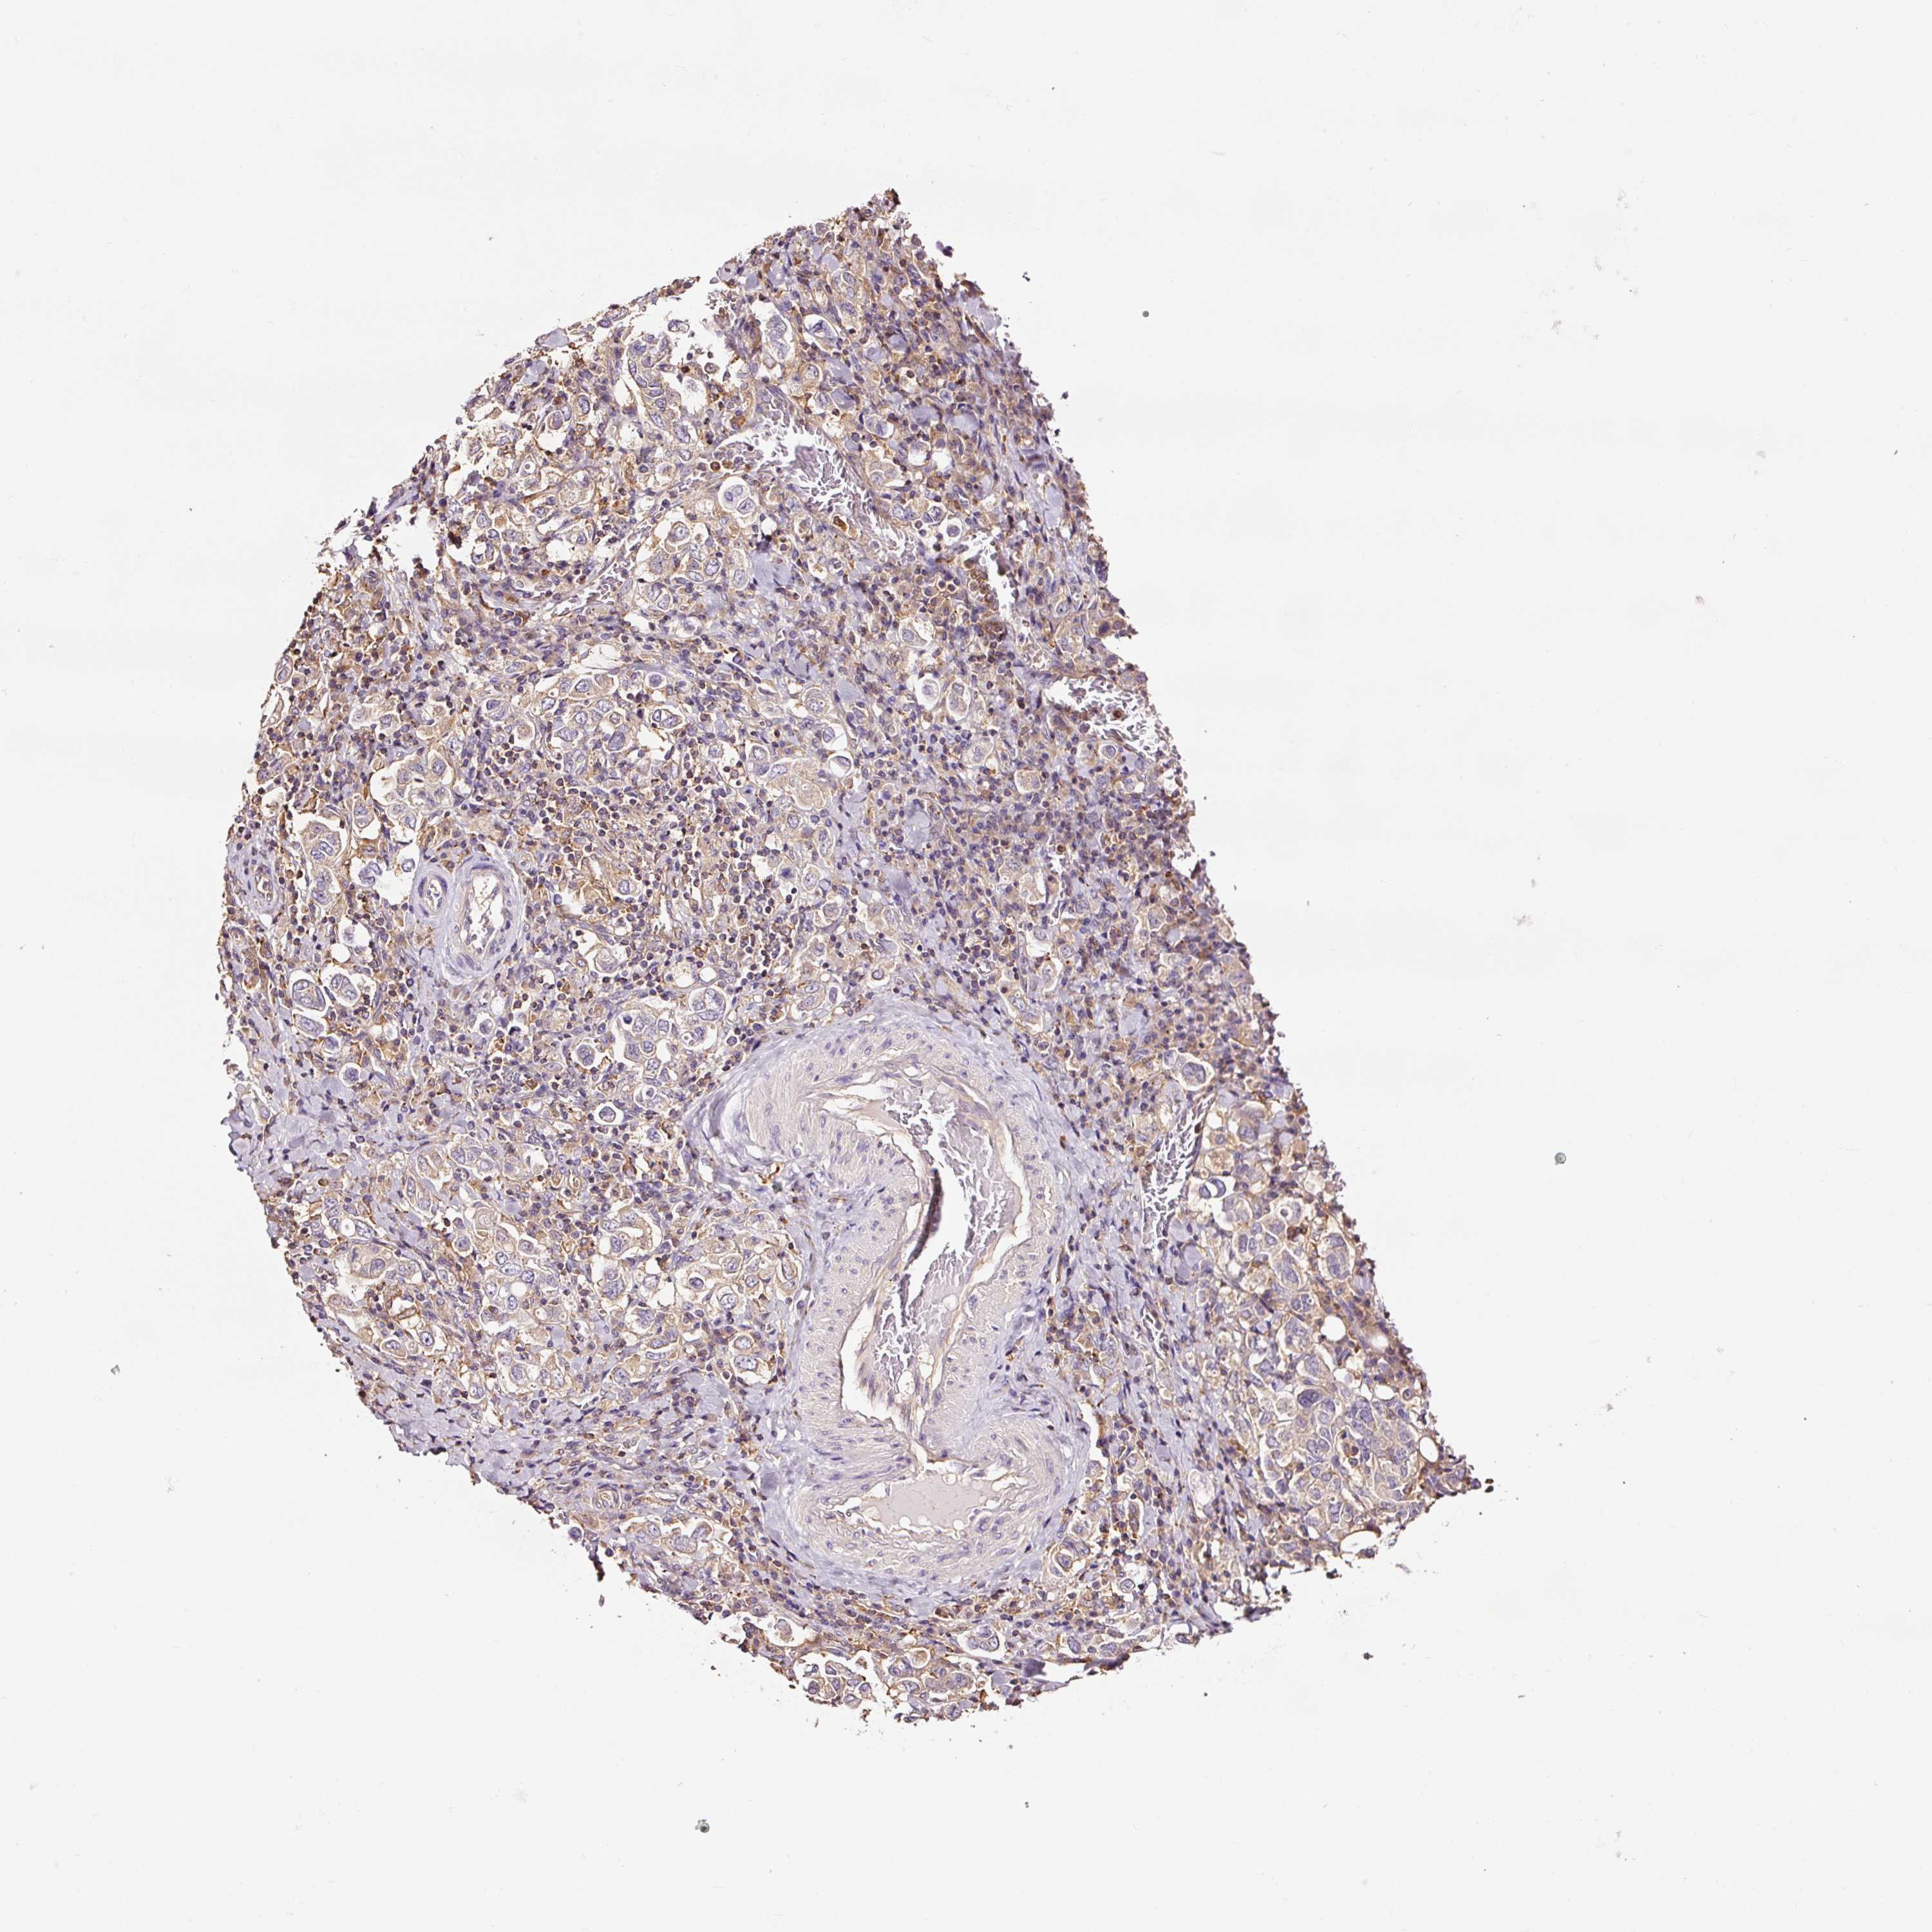

STOMACH CANCER - Protein expressioni

A mouse-over function shows sample information and annotation data. Click on an image to view it in a full screen mode. Samples can be filtered based on level of antibody staining by selecting one or several of the following categories: high, medium, low and not detected. The assay and annotation is described here.

Note that samples used for immunohistochemistry by the Human Protein Atlas do not correspond to samples in the TCGA dataset.

Antibody stainingi

Antibody staining in the annotated cell types in the current human tissue is reported as not detected, low, medium, or high, based on conventional immunohistochemistry profiling in selected tissues. This score is based on the combination of the staining intensity and fraction of stained cells.

Each image is clickable and will lead to virtual microscopy that enables deeper exploration of all samples and also displays staining intensity scores, fraction scores and subcellular localization as well as patient and tissue information for each sample.

Antibody HPA037997

Antibody HPA037998

Antibody CAB025485

Staining

Adenocarcinoma, NOS